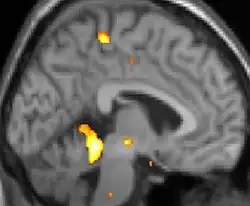

| La tomographie par émission de positons (TEP) montre les zones du cerveau étant activées durant la douleur | ||

Les images par tomographie à émission de positron indiquent les régions du cerveau qui sont activées lors de la douleur, par rapport aux périodes sans douleur. Elles montrent les régions du cerveau qui sont toujours actives durant la douleur en jaune/orange (appelé "matrice-douleur"). La zone au centre (dans les trois vues) est spécifiquement activée uniquement pendant la crise. Les photos sur la ligne du bas (effectuées par VBM) montrent les différences structurelles entre les patients souffrant d'AVF et des personnes saines : seulement une partie de l'hypothalamus est différente[50],[51].